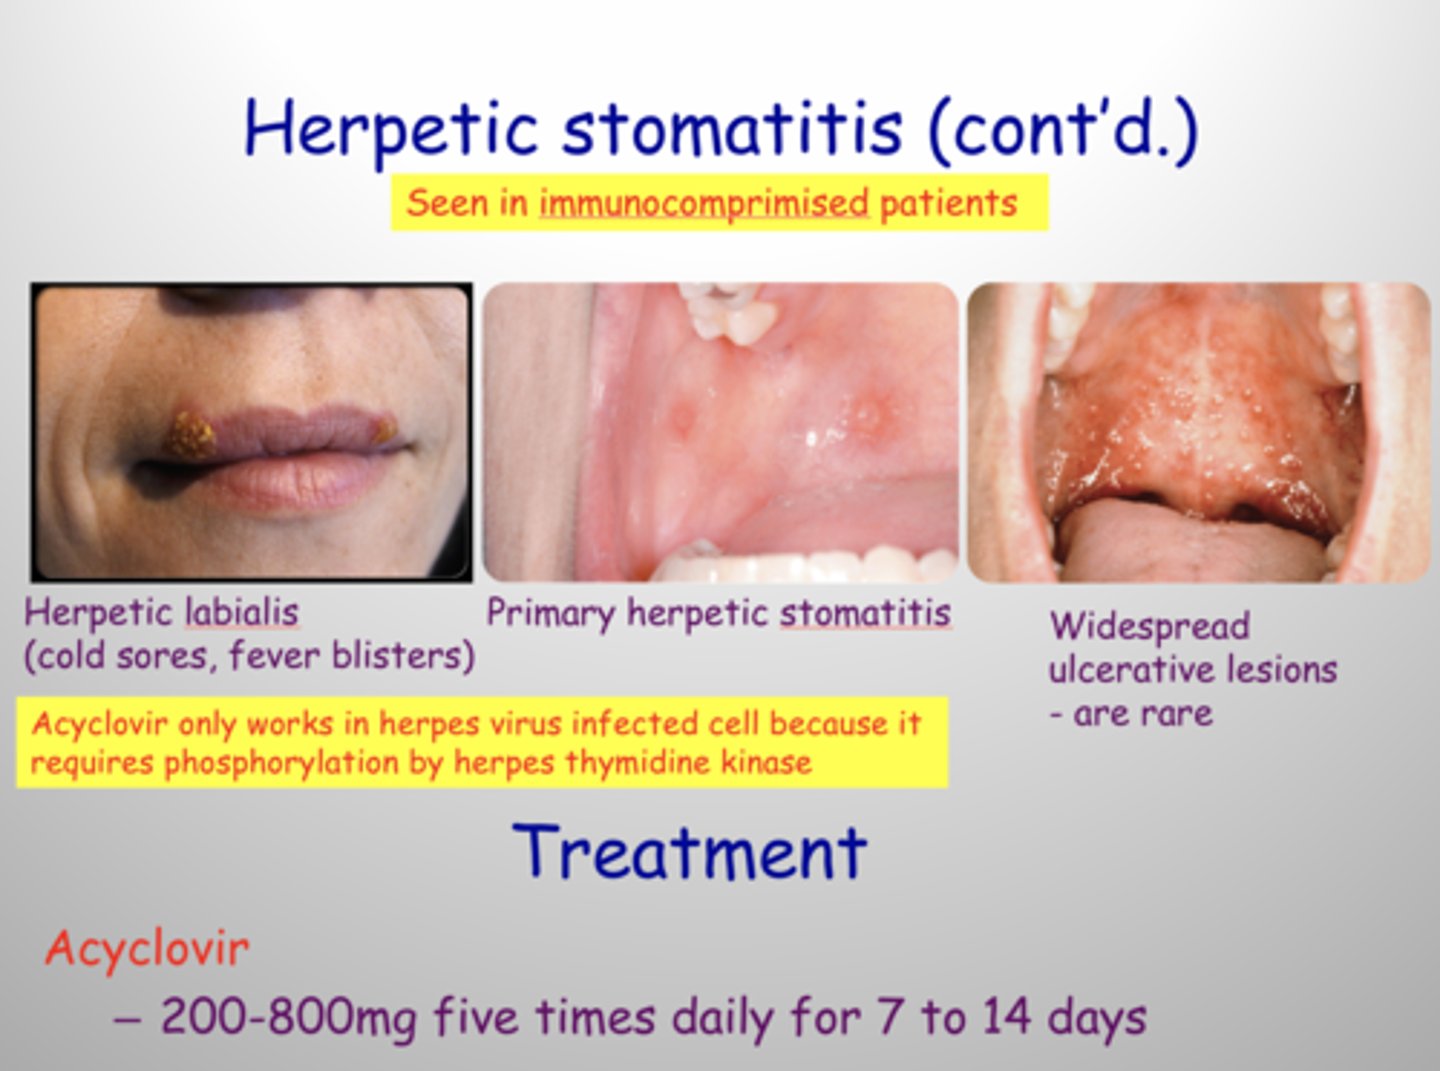

Name the pathology: viral infection causing oral ulcers and inflammtion. Mainly affects the children

TX: (3)

herpetic stomatitis

tx: acyclovir, liquid diet and numbing medication , lidocaine rinse if pain severe